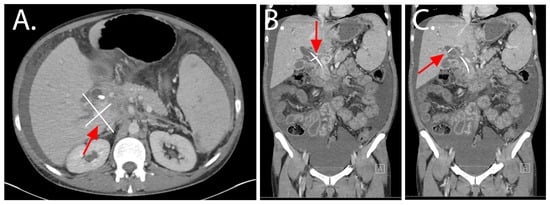

2.3. Index Hospitalization